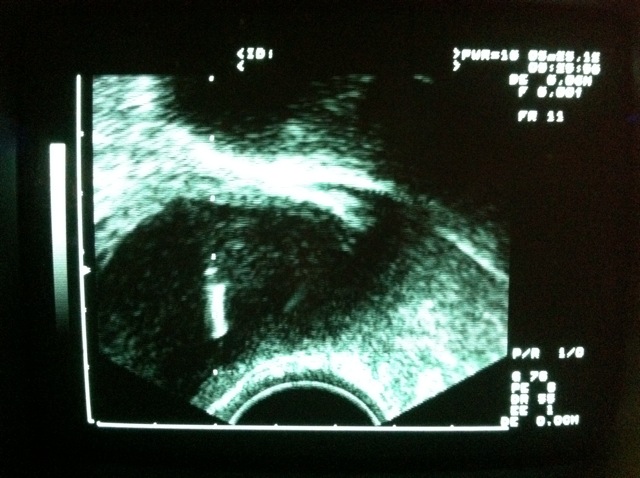

北部1對結婚11年的夫妻,因妻子患有陰道痙攣症,從未行房成功。因年屆40有生子壓力,日前到診所進行麻醉下人工授精,丈夫卻順道向醫師提出「剪開處女膜」以成功進行性行為的需求。雖經醫師提醒處女膜與陰道痙攣症無關,但在病患堅持與簽下切結書後,妻子除順利完成人工授精,更在丈夫的「監工」下,執行處女膜剪開手術。

執行手術的婦產科醫師蔡鋒博表示,陰道痙攣(Vaginismus)是一種影響女性性行為能力的病症。可發生於各種形式的陰道插入中,包括性行為、婦科檢查中的陰道插入等。由於恥尾肌的條件反射行為,導致陰道內壁肌肉突然猛烈收縮,從而使得包括性交在內的任何陰道插入行為產生疼痛、無法完成。

蔡鋒博醫師表示,陰道痙攣多屬心因性引起,所以可能會運用到心理療法,國外也有以人工陰莖由小到大號,漸進式治療約半年至1年,成功率可達95%。但個案要求「剪開處女膜」以成功進行性行為的需求,一聽卻直搖頭。強調兩者根本沒有關係,也不代表將來性生活會正常化。他說:「先生跟太太甚至異口同聲的請求,且態度誠懇認真,不像是在開玩笑!」

依醫師法、醫療法及醫學倫理:病人的要求,若不違反醫學原則,可依病人要求,進行醫療程序,但病人要寫切結書在病歷。太太當進行完人工受精之後,就請先生進穿手術衣,戴無菌的手術套開刀房,在丈夫的「監看」下,由醫師在處女膜6及12點鐘方向各剪開一刀,然後進行止血的動作。

蔡鋒博醫師說:「還是頭一次遇到婦產科醫師被要求幫病人剪開處女膜!」即使手術成功,對於夫妻來說說,並不代表將來性生活就無礙,因陰道痙攣症重點在心理層面並非在處女膜。還是應該尋求心理諮商師,或是精神科等,協助幫忙解決問題,才是治療陰道痙攣症的正確之道。